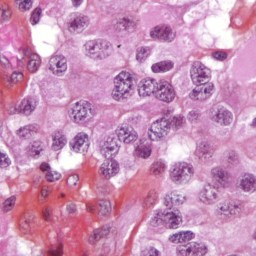

Clean meat is produced by taking stem cells from an animal and placing them in a nutrient-rich environment to encourage them to grow. Dutch researcher Mark Post ate the first “clean” burger in 2013, but its $330,000 price placed it far outside the realm of the everyday McDonald’s menu, and new research suggests the meat could hit shelves by 2021 with a price tag of $10 per patty — but the nutrients used to feed the cells are expected to be a major factor in the final price, and the eventual adoption and consumption of these types of meats.